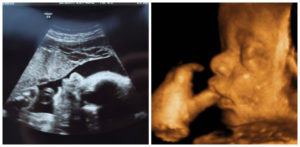

Скорее всего, вы уже прошли последнее ультразвуковое исследование, во время которого была окончательно установлена предполагаемая дата родов. Но бывает, что УЗИ назначают и на 37 неделе беременности для уточнения ряда моментов.

Специалист во время ультразвуковой диагностики на 37 неделе внимательно осмотрит ребеночка и степень его развития, зафиксирует основные параметры, сердцебиение, оценит состояние и количество околоплодных вод, состояние матки и шейки, пуповины, степень зрелости плаценты. Скорее всего, будет проведена также допплерография для оценки маточно-плацентарного кровотока.

Снимки УЗИ на 37 неделе